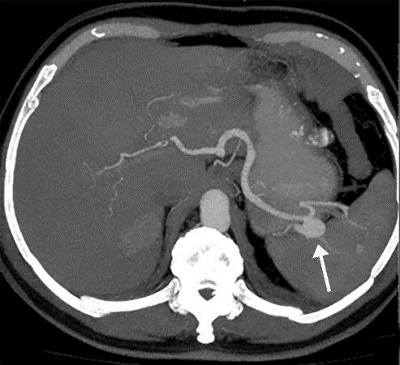

Milzarterienaneuysma

Nachweis eines Milzarterienaneurysmas in der CT-Angiographie.